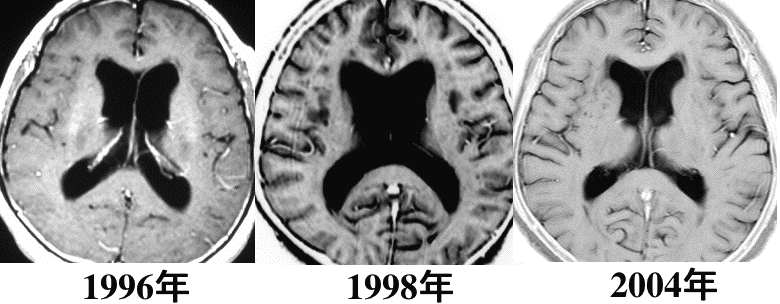

8年間観察したら自然に良くなった聴神経腫瘍に合併する水頭症です。しかし,水頭症が自然寛解することはほとんどないことです。

水頭症の自然寛解